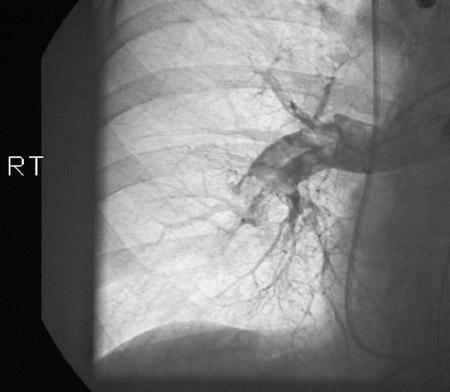

![]() | These views appear during a thoracic CT angiogram and demonstrate evidence for multiple pulmonary thromboemboli seen above on the left and below on the right. There should be contrast filling pulmonary arteries into the periphery. This patient's risk factors included age, history of smoking, and immobilization during prolong hospitalization for bowel obstruction. |